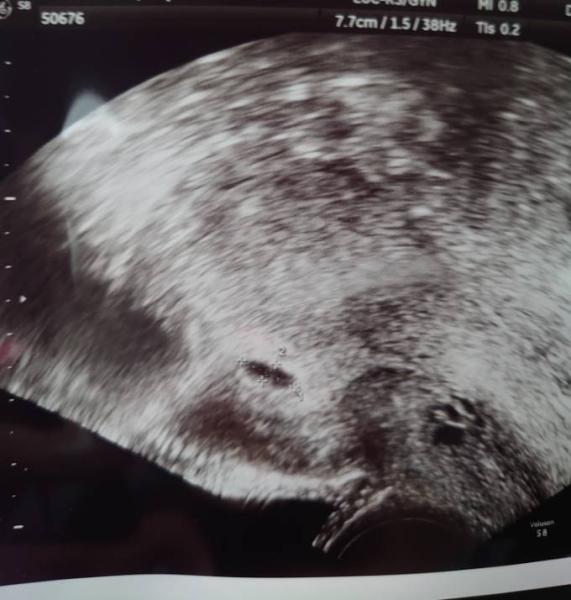

Danke an alle.. leider hat man noch nicht so viel gesehen. Naja es ist auf jeden Fall was drin, das beruhigt mich schon sehr aber die Ärztin war unsicher und will daher am Montag nochmal nachschauen. Hauptsache es ist ein Dottersack und eine Anlage sichtbar... oder ? Bin hin und hergerissen was ich davon halten soll. Sie wird nun HCG messen.

Bild zu